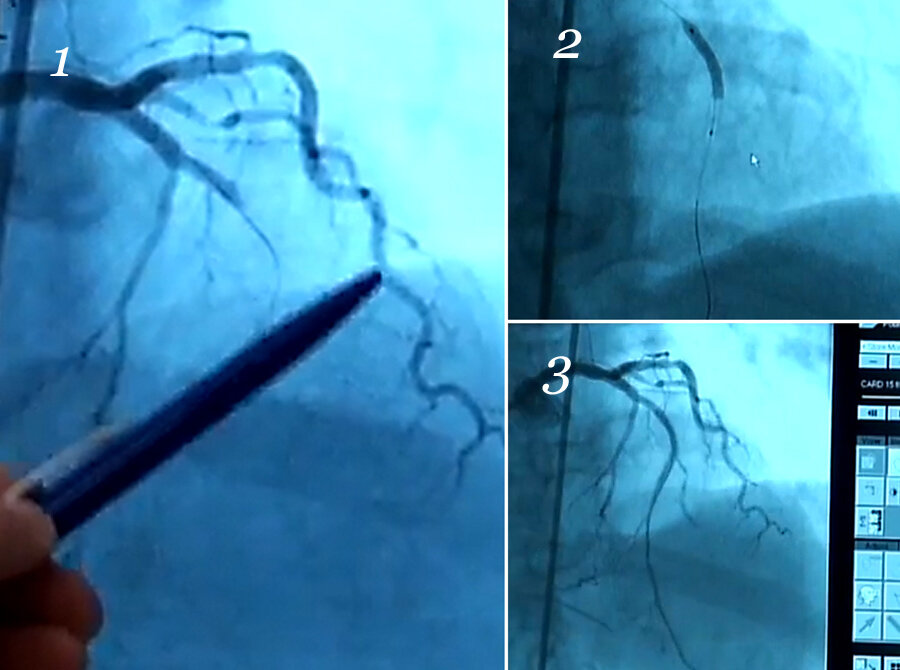

А вот как стент работает. Это скриншоты с рентгенотелевизора.

На первой картинке мы видим только одну артерию, кудрявую такую. Но должна быть видна еще одна, под ней. Из-за бляшки ток крови полностью перекрыт.

Толстая колбаска на второй - стент, который только что развернули. Артерии не видны, потому что в них не запущен контраст, но проволочки как раз видно.

Третья показывает результат. Артерия проявились, кровь потекла. А теперь еще раз сравните первую картинку с третьей.